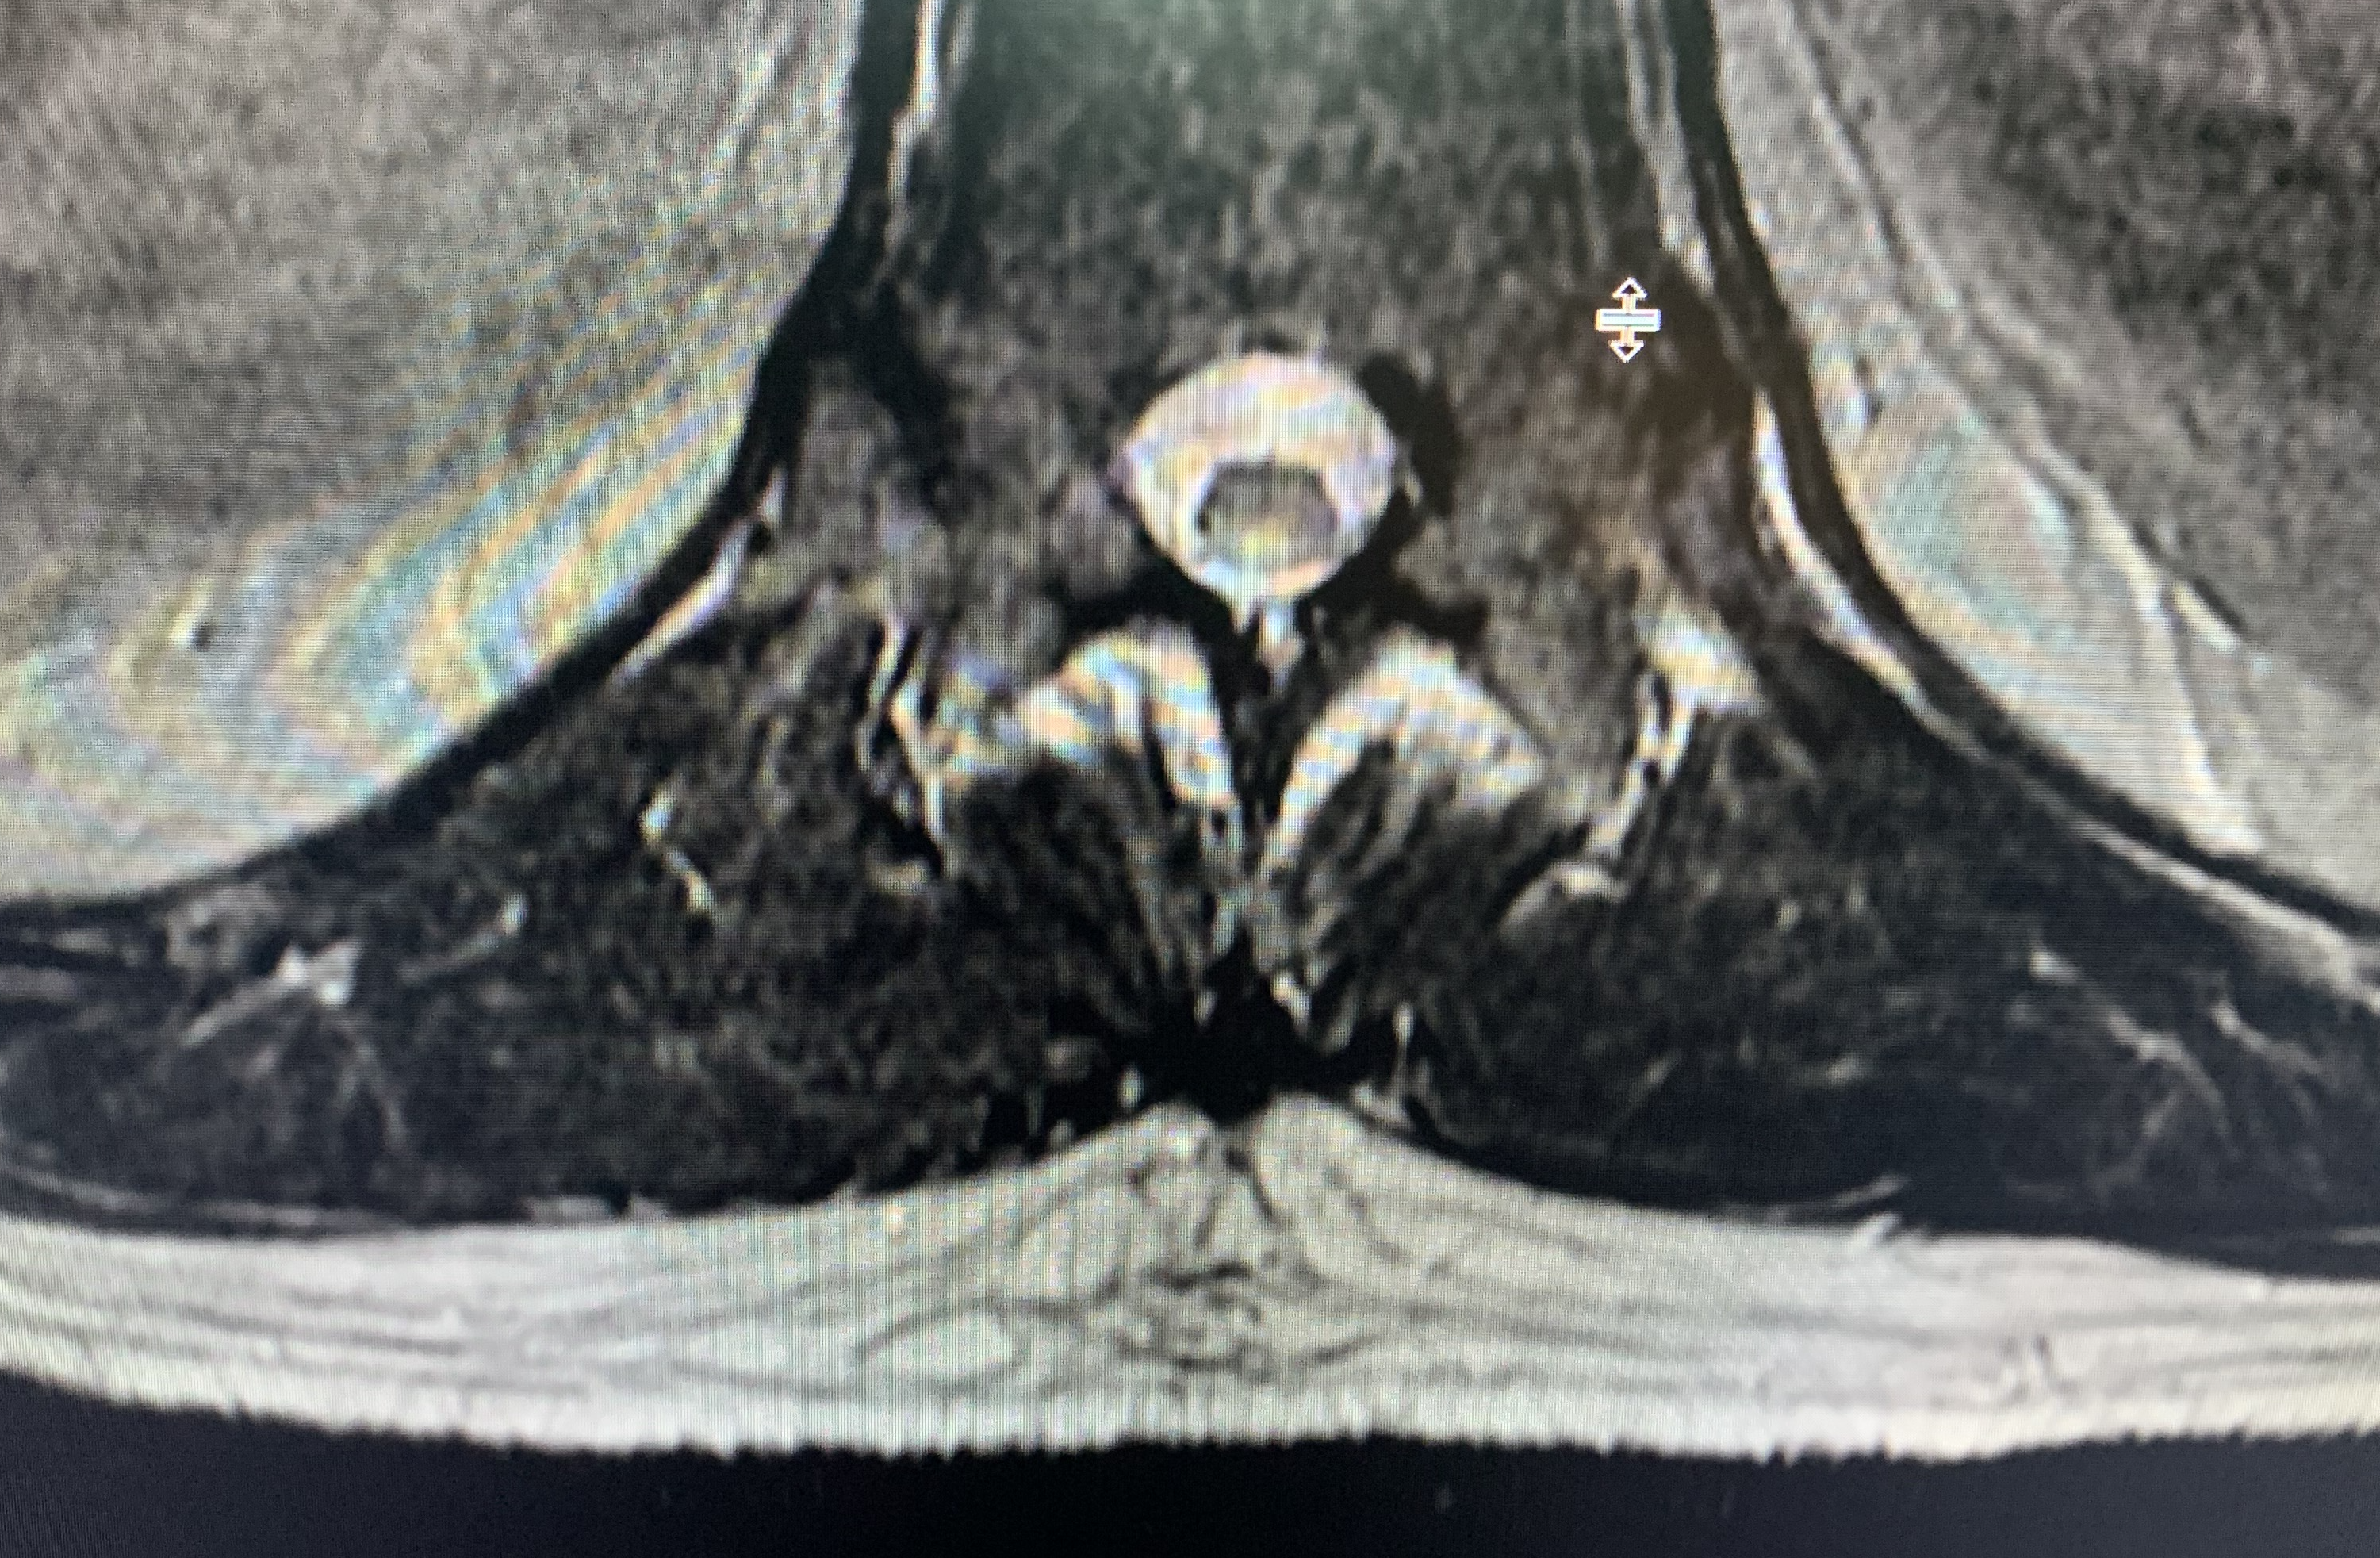

Thoracic MRI showed an abnormal cord signal involving the posterior columns at the T11-T12 level (Figure 1).

Figure 1. Thoracic MRI showed an abnormal cord signal involving the posterior columns at the T11-T12 level.

The key diagnostic features of SCD are early involvement of the posterior and lateral columns of the spinal cord presenting as paresthesias and proprioceptive loss without motor or autonomic deficits.10 Markers of spinal cord inflammation include an elevated CSF protein level with absent oligoclonal bands/immunoglobulin G index and absent CSF pleocytosis.10 The characteristic MRI findings are symmetrical T2 hyperintensity within the posterior columns, with or without lateral column involvement.11 This produces the classic inverted V sign on axial T2-weighted images.12